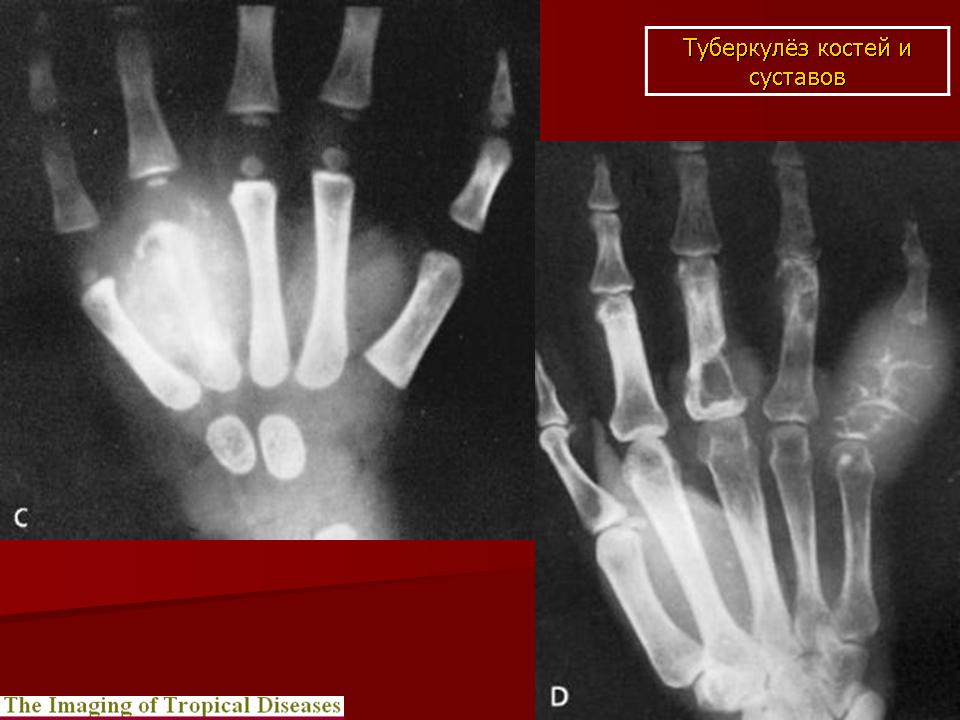

Медицинские аспекты заболеваний: рентгенологическая картина туберкулеза костей

Раздел: Снимки-откровения